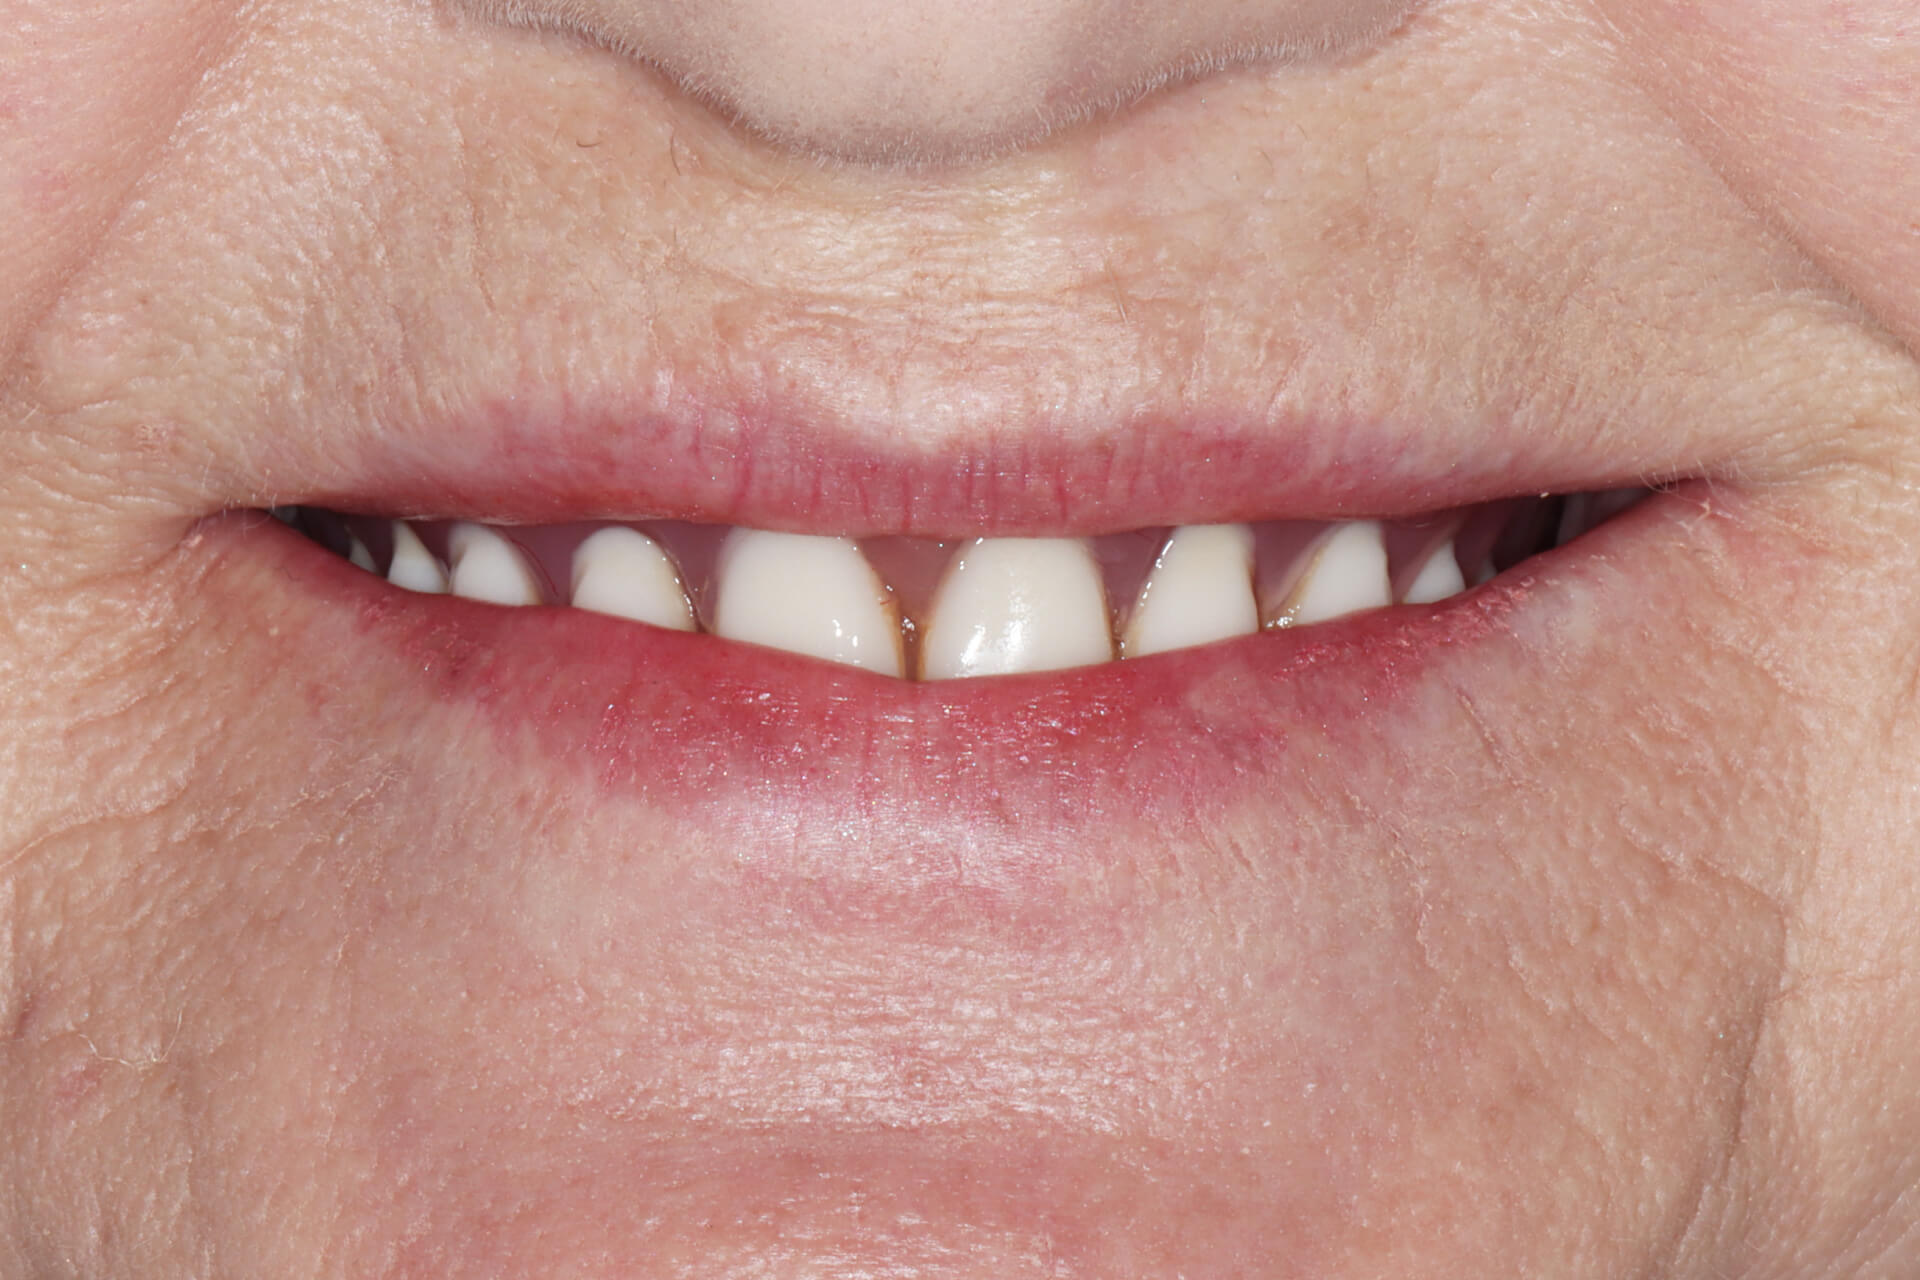

Leczenie Krystyny

Krystyna

All-on-X

- Problem

Pani Krystyna trafiła do nas z bezzębiem w górnym łuku i oczekiwaniem na szybkie, ale trwałe rozwiązanie.

- Leczenie

Zdecydowaliśmy się na leczenie w technologii All-on-X z obciążeniem natychmiastowym – już tego samego dnia po wszczepieniu implantów Pacjentka otrzymała tymczasowy most protetyczny, który pozwolił jej od razu cieszyć się nowym uśmiechem. To przykład, jak nowoczesna implantologia może zmienić życie w ciągu jednego dnia.